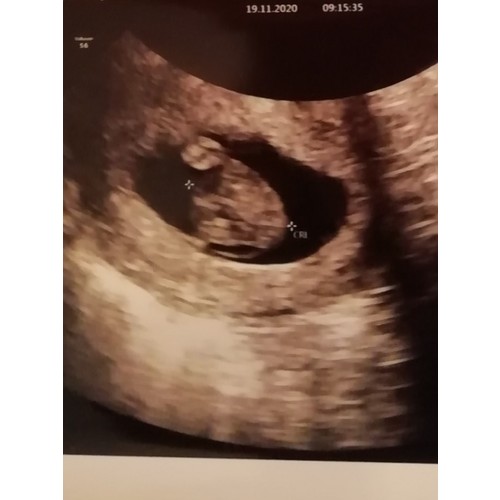

Ik dacht 7w3d te zijn gisteren. Uiteindelijk gemeten op 7w6d en hartje klopte duidelijk 🥰

Mijn echo is ook van gisteren ben 7+4 daar. Hartje kon je duidelijk zien flikkeren.

Volgens de arts 6+4, volgens m’n eigen berekening was ik al een week verder

Alles in orde en een kloppend hartje 🙏🏻